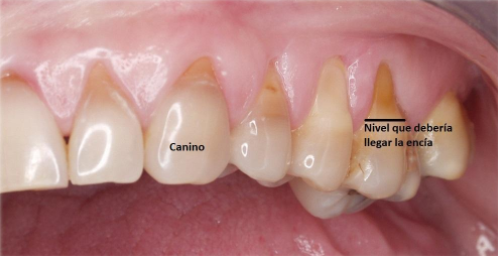

Debido en parte a lo explicado anteriormente, la mayoría de los pacientes nos llegan con pérdida de hueso en los dientes posteriores (premolares y molares) que observamos por el recogimiento de las encías, y que le quedan los cuellos dentales expuestos (que llamamos recesión gingival) que no es más que una pérdida de hueso. Al examinar, notamos que es porque los caninos están cortos o no cumplen su función de separar las piezas dentales posteriores (ver foto).

Por eso, necesitamos examinar y mirar toda la boca, incluyendo unas radiografías panorámicas (vea foto de radiografía panorámica) y no asistir sólo por dolor. Mire su boca desde un punto de vista de prevención, sin caries, sin tapaduras, sin ausencia de muelas, sin molestias musculares (bruxismo) de la boca, cuello o dolores de cabeza.